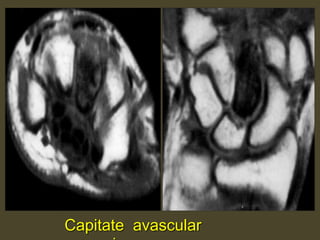

Capitate avascular